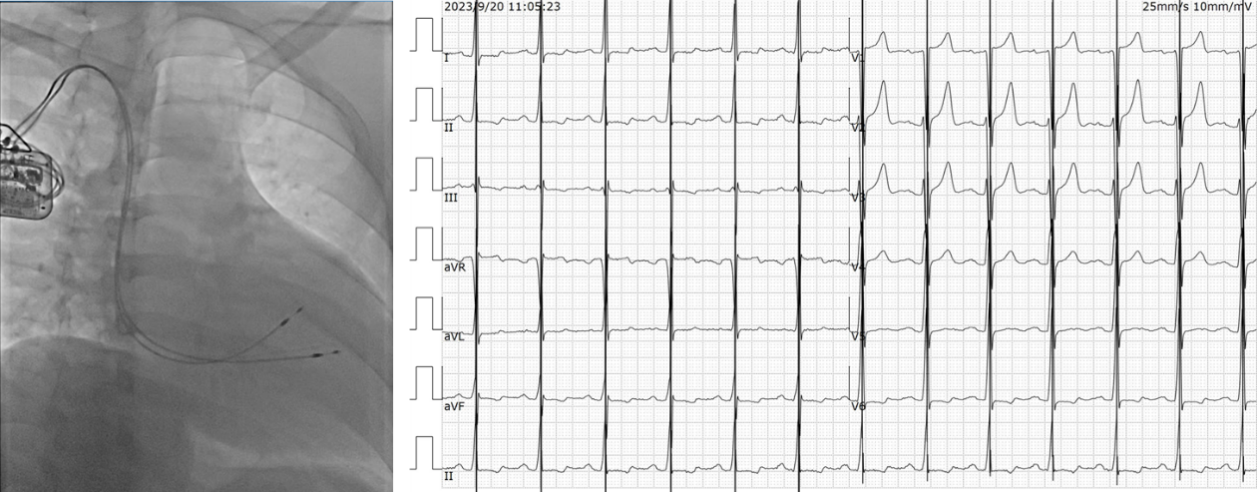

上图所示是一位慢性终末期心衰患者,植入CRTD前心脏扩大,左室内径为76mm,左室射血分数(LVEF):18%,在植入了CRTD一年后复诊扩大的心脏有所回缩,左室内径为66mm,左室射血分数(LVEF)提高到了35%。患者自觉活动后呼吸困难明显好转。

上图所示病例是一位32岁的扩张性心肌病患者,其左室射血分数(LVEF)仅为29%,在植入了心肌收缩力调节器(CCM)一个月后随访,自觉胸闷及气促等症状明显缓解,对该病例的随访还在进行中。